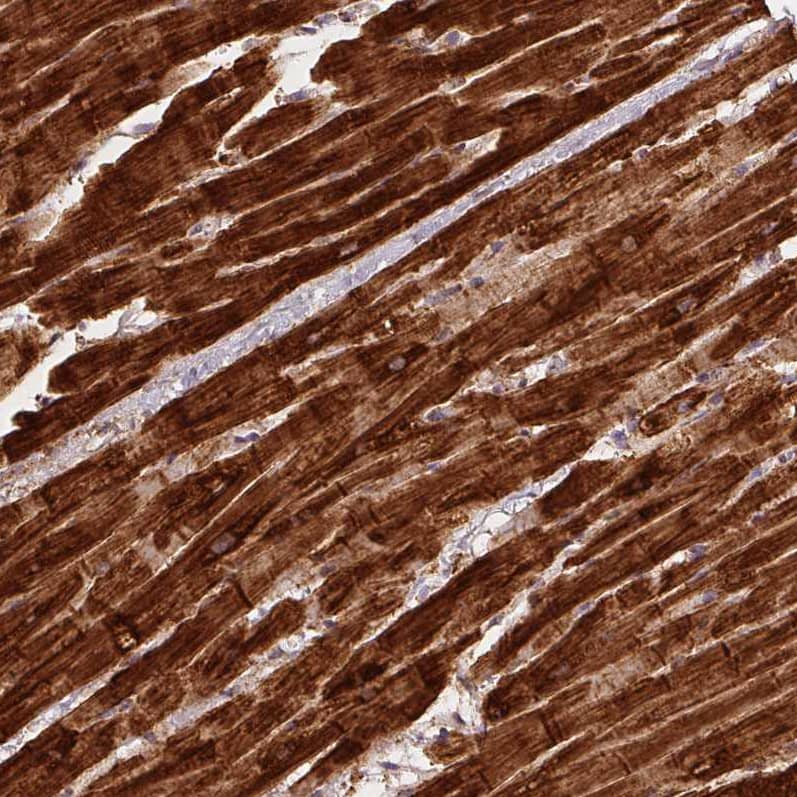

Staining of human heart muscle shows strong cytoplasmic positivity in cardiomyocytes.